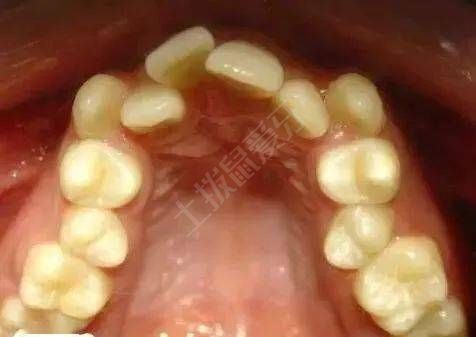

牙列擁擠是指個別牙或多個牙在各個方向的錯位,如唇舌向錯位、近遠中錯位、高位低位、扭轉(zhuǎn)等。牙列擁擠分為三度:輕度擁擠、中度擁擠、重度擁擠。其中擁擠度0~4mm稱輕度擁擠,5~8mm為中度擁擠,8mm以上則為重度擁擠。

擁擠度通過目測只能得出大概數(shù)值,而正畸矯治計劃的設(shè)計需要具體數(shù)值,所以臨床上,醫(yī)生們通過制取口內(nèi)硅橡膠或藻酸鹽模型來測量擁擠度,用患者應(yīng)有牙弓長度減去患者現(xiàn)有牙弓長度即可得出擁擠度。通過測量結(jié)果判斷是否需要拔牙以及拔牙后間隙如何分配等具體設(shè)計。牙列擁擠會導致食物嵌塞,患者不容易清潔,容易出現(xiàn)齲齒。牙列擁擠容易形成牙結(jié)石導致咽炎、牙周炎,導致牙齦和牙槽骨萎縮,最終形成牙周病,導致牙列缺失。所以出現(xiàn)較嚴重的擁擠,要及時進行治療,防止出現(xiàn)更嚴重的后果。